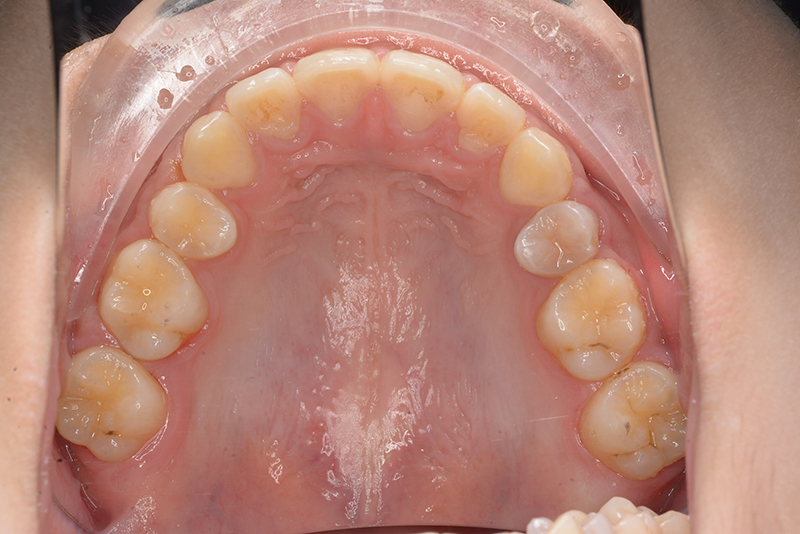

初診時

FP・IOP

口腔内所見 大臼歯関係は右側がエンドオンのclassⅡ、左側がfull classⅡ。 上顎正中は下顎正中に対して僅かに右側偏位しており、上顎前歯は大きく唇側傾斜しover jetが11.0mmと上突咬合を呈していた。また下顎歯列の緩やかなスピーカーブのため過蓋咬合(over biteは5.0mm)となっていた。